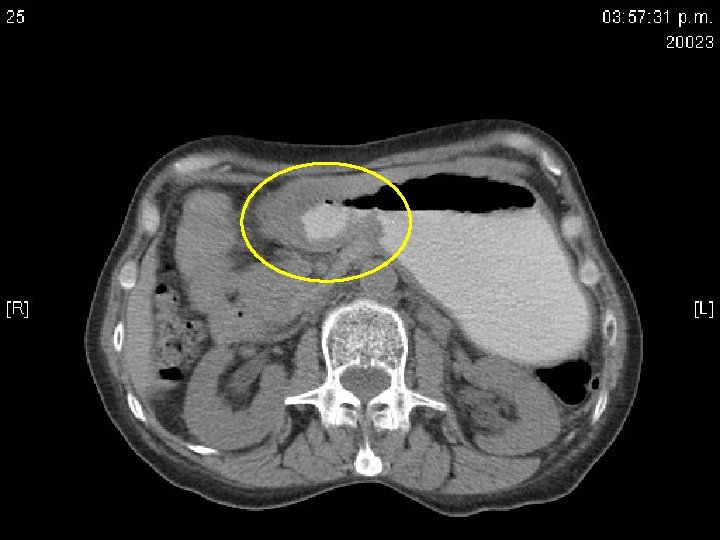

Tomografía abdominal • Hígado con presencia de nódulo de 10 mm en el segmento 3. • Estómago distendido con abundante contenido liquido en el fondo con paredes gruesas a nivel del antro de 12 mm que condicionan estrechez de la luz, infiltran duodeno. • Infiltración de la grasa perigástrica que infiltra páncreas. No se definen adenopatías adyacentes. • CC: quiste hepático. NM gástrico con infiltración a páncreas y grasa perigástrica, cabeza de páncreas prominente.

TAC: signos tomográficos